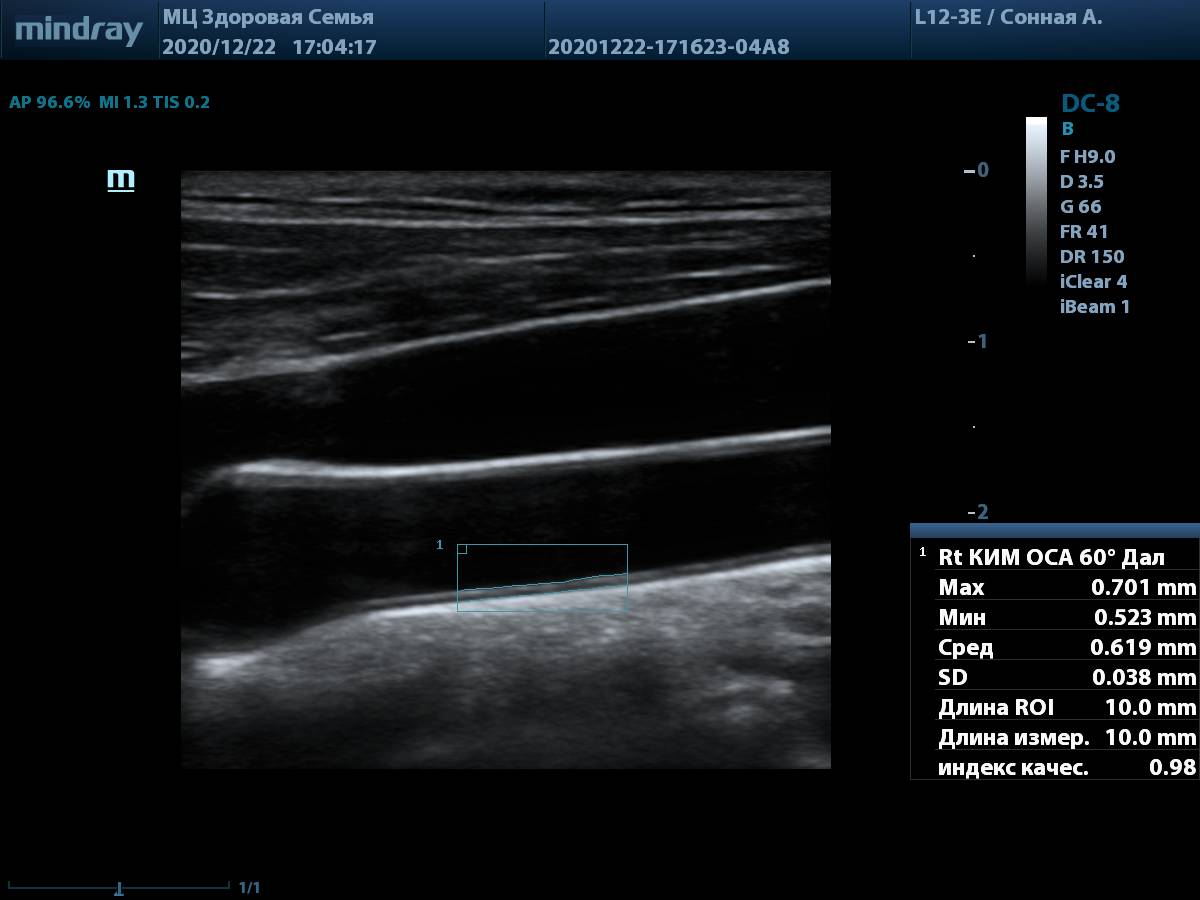

8. Общая сонная артерия (L12-3E) с использованием системы автоматического измерения комплекса интима-медиа, согласно международным стандартам.